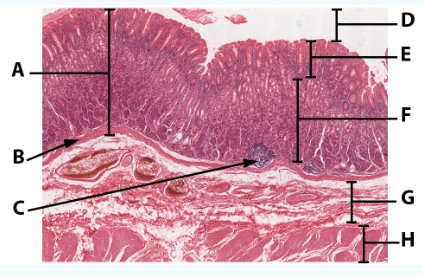

A

Mucosa: simple columnar epithelium with microvilli

B

Submucosa

C

muscularis mucosa

Area

Small intestine

E

simple columnar epithelium with goblet cells and microvilli

F

Villi

G

Lamina propria